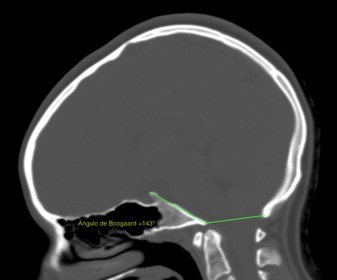

扁平颅底是颅颈区的一种先天性骨畸形,常并发颅底凹陷症。其诊断方法是根据颅骨侧位片测量颅底角,即蝶鞍与斜坡形成的角度,正常值为115°-140°;当患者颅中窝、颅前窝底部和颅底斜坡部均向颅内凹陷,使颅底角大于140°,我们将诊断为颅底扁平或扁平颅底。

图1-CT片上见到的扁平颅底。